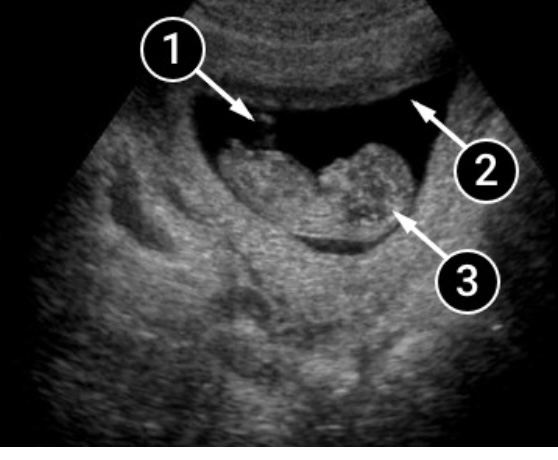

En esta imagen, el bebé esta flotando en el líquido amniótico, apoyándose cómodamente en las paredes del saco amniótico. La imagen de perfil del bebé te brinda la oportunidad de apreciar el botón nasal y el pliegue nasal, las mejillas, la boca e incluso una pequeña oreja, ubicada justo un poco por debajo de la posición normal.

La cabeza del bebé todavía es muy grande, casi la mitad del tamaño del cuerpo. Pero ya está ligeramente erguido y se ve un pequeño cuello. En el área del tórax, puedes ver un punto, es el corazón!. Las piernas no son visibles, pero se alcanza a ver el contorno de la mano derecha.

El bebé nada en el líquido amniótico, que se representa en la imagen como un gran contorno oscuro. La espiral es el cordón umbilical que proporciona una conexión estrecha entre la mami y el bebé. La sangre fluye a través de sus vasos conectados con la placenta. Está proporcionando nutrición y oxígeno imprescindible para su desarrollo.

- Cordón umbilical.

- Líquido amniótico

- La cabecita del bebé.